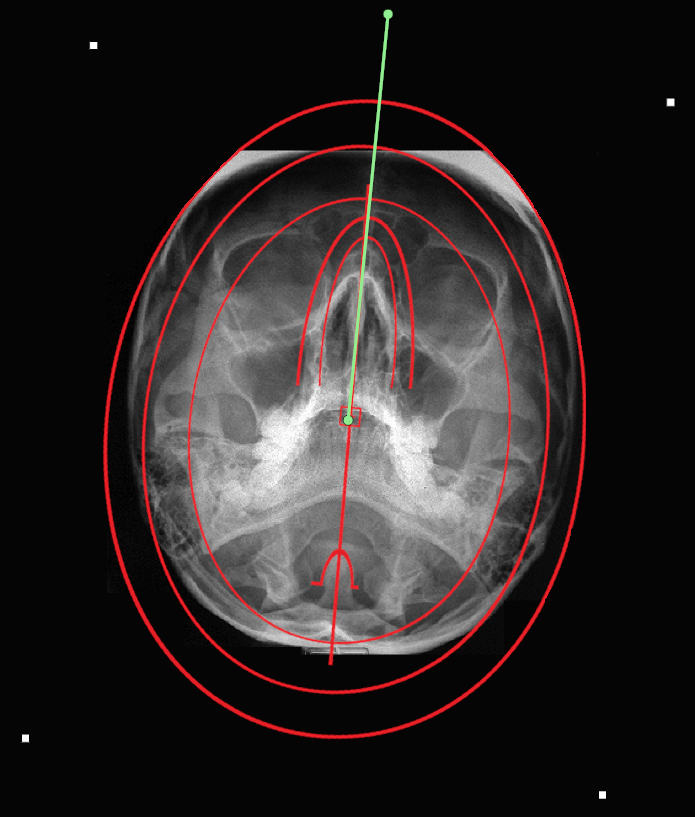

9.5.10. Atlas Horizontal Template

The atlas horizontal template is used to find the vertex skull line (horizontal cephalic line). Follow the instructions below to use this tool:

1.      Select the ‘Atlas Horizontal Template’ from the advanced section of the chiropractic toolbox

2.      Click on the image and a template will appear. If the image is not calibrated, you will be prompted to calibrate the image.

3.      To move the template: click on the template and drag it to the desired location.

4.      To resize the template: click on the any of the white points located on the outer corners and move it to adjust the dimensions.

5.      To rotate the template: click on the green point and a wheel will appear for you to click and rotate the template.

An example of this template is shown below: